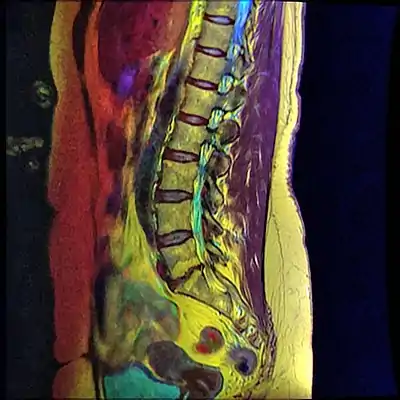

A retrolisthesis is a posterior displacement of one vertebral body with respect to the subjacent vertebra to a degree less than a luxation (dislocation). Retrolistheses are most easily diagnosed on lateral x-ray views of the spine. Views where care has been taken to expose for a true lateral view without any rotation offer the best diagnostic quality.

Retrolistheses are found most prominently in the cervical spine and lumbar region but can also be seen in the thoracic area.

Pain may be experienced as a result of irritation to the sensory nerve roots by bone depending on the degree of displacement and the presence of any rotatory positioning of the individual spinal motion segments. The soft tissue of the disc is often caused to bulge in retrolistheses. These cannot be determined by plain films, as the x-ray passes through the soft tissue. A study by Giles et al., stated that sixteen of the thirty patients (53%) had retrolisthesis of L5 on S1 ranging from 2–9 mm; these patients had either intervertebral disc bulging or protrusion on CT examination ranging from 3–7 mm into the spinal canal. Fourteen patients (47%) without retrolisthesis (control group) did not show any retrolisthesis and the CT did not show any bulge/protrusion. On categorizing x-ray and CT pathology as being present or not, the well positioned i.e. true lateral plain x-ray film revealed a sensitivity and specificity of 100% ([95% Confidence Interval. = [89%–100%]) for bulge/protrusion in this preliminary study.” (7)

Since the vertebral body in a retrolisthesis moves in a posterior direction, the grading used for spondylolistheses is of little use. It is however useful to divide the anterior to posterior dimension of the intervertebral foramina (IVF) (4) into four equal units. A posterior displacement of up to ¼ of the IVF is graded as Grade 1, ¼ to ½ as Grade 2, ½ to ¾ as Grade 3, ¾ to total occlusion of the IVF as Grade 4. Alternatively, a measurement of the amount of displacement can also made by measuring the bone displacement in millimetres.

Associated radiological findings include a vacuum phenomenon (in the nucleus pulposis of the adjacent intervertebral disc), reduction of disc height with corresponding loss of the disc space, marginal sclerosis of the adjacent vertebral bodies, osteophyte formation and apophyseal joint instability. With a retrolisthesis there is always a less than ideal positioning of spinal segments. There is also always a reduced anterior to posterior dimension of the spinal canal compared to the way it is supposed to be. The greater the posterior displacement, the more significant it is for producing a dysfunctional spinal cord or even a cauda equina syndrome.